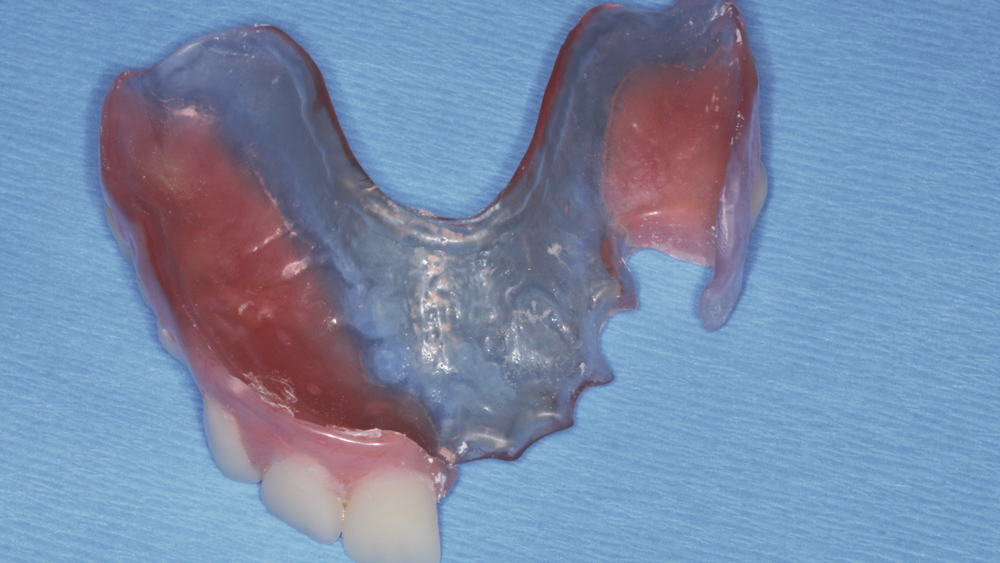

Esthetics and occlusion can be challenging in these types of cases. Restoring half an arch and trying to mirror the contralateral soft tissue and dentition with proper contours and shade requires patience and resolve. The lab provided a PMMA try-in prosthesis, which I evaluated with Weldon. The try-in allowed us to easily resolve any discrepancies with the prosthetic design and develop ideal occlusion. Once Weldon agreed on the esthetics, the PMMA provisional was returned to the lab and duplicated in BruxZir Solid Zirconia. This extra step eliminates excessive chairside adjustments upon seating of the final prosthesis.

The PMMA try-in prosthesis ... allowed any necessary adjustments to easily be made to the prosthetic design prior to milling the final BruxZir restoration.